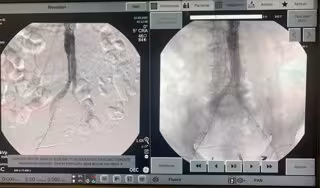

"Desde nuestra compañía llevamos años acompañando esta evolución de la práctica de cirugía vascular e implementando avances tecnológicos de arcos móviles y quirófanos híbridos que permitan responder a estas nuevas problemáticas médico-quirúrgicas relativas a la reducción de dosis, ya que los procedimientos se hacen guiados por rayos X; a la reducción del contraste iodado utilizado, que permite opacificar los vasos de acceso a ser tratados; y a la optimización del flujo de trabajo , en tanto que algunos de estos procedimientos complejos pueden durar más de 10 horas", explica.

Los procedimientos mínimamente invasivos mejoran la respuesta postoperatoria del paciente, reducen los tiempos de hospitalización y optimizan costes. Un triple beneficio que fundamenta el desarrollo de tecnologías de guía de imagen, tanto los quirófanos híbridos como los arcos quirúrgicos que facilitan, entre otras muchas intervenciones, la reparación de aneurismas de aorta abdominal por vía endovascular.

En este sentido, Ayestarán explica que "los arcos constituyen una herramienta decisiva para especialistas en cirugía vascular al agilizar la toma de decisiones en quirófano evitando traslados del paciente y ofrecen mayor resolución, claridad, y contraste en las imágenes".